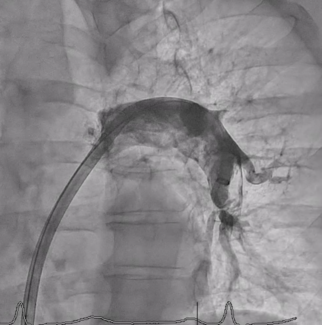

Angiographic and procedural characteristics are summarized in Table 2. Approximately 47.6% of patients had an anterior infarct and 37.4% had an inferior infarct. Transradial approach was employed in most cases, with a good representation of direct stenting technique (>40%). Approximately 42.2% and 28.9% of patients had mechanical thrombectomy and staged revascularization, respectively. Of note, mechanical circulatory support was only needed in 4% of cases. Regarding lesion site, 30.6% of patients had a bifurcation lesion as a culprit, mean lesion length was ~25 mm (consistent with an average stent length of ~33 mm), and multivessel disease was present in 53.3% of patients. Angiographic results were good, with almost all patients reaching Thrombolysis in Myocardial Infarction 2-3 flow post procedure.

Kaplan-Meier analysis showed a DOCE-free survival rate of 96.6% at 6 months, 96.3% at 1 year, and 93.8% at 3 years (Figure 1). Notably, we observed post hoc a significantly higher cumulative incidence of adverse events at 1-year follow-up among diabetics (8.0% vs 2.2%; log rank P=.01) (Figure 2) and chronic kidney disease subgroups (9.4% vs 2.4%; log rank P<.01) (Figure 3).